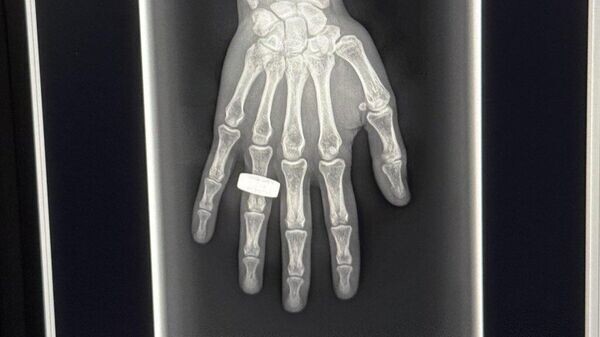

Рука астронавта с кольцом стала первым рентгеновским снимком в космосе

"В течение первых двух полных дней на орбите экипаж сделал первый в истории рентгеновский снимок в космосе – спустя 130 лет после того, как был получен первый рентгеновский снимок", – говорится в сообщении.

В компании отметили, что астронавты повторили открытие Вильгельма Рентгена, который в 1985 году получил на фотопластине первое рентгеновское изображение – руки своей супруги с надетым на палец кольцом.

Представитель KA Imaging Карим Карим в интервью телеканалу CBC сообщил, что примененная для первого рентгена в космосе технология разрабатывалась в Канаде. Он отметил, что ранее подобные эксперименты на орбите не проводились, так как существовала проблема с размерами и весом рентгеновских аппаратов. Однако KA Imaging сумела создать весьма легкую модель, которую и отправили в космос. По его словам, эта технология поможет астронавтам оставаться в космосе более длительное время.